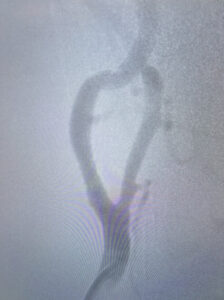

Ένδαγγειακή αντιμετώπιση καρωτιδικής νόσου